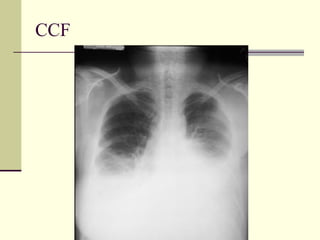

Pulmonary Interstitial Edema   1. CHF 2. Lymphangitic spread 3. Allergic reaction

CHF

Pleural Effusion   1. CHF 2. Mets 3. Pancreatitis 4. Pulmonary embolism 5. Trauma 6. Empyema 7. Collagen vascular 8. Ovarian tumor (Meig’s Syndrome) 9. Chylothorax

CCF